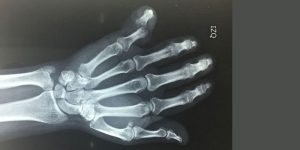

Mano

Las patologías de mano son habituales, especialmente en las personas adultas. Provocan pérdida de función y movilidad en la extremidad superior, afectando ampliamente a las actividades de la vida diaria.